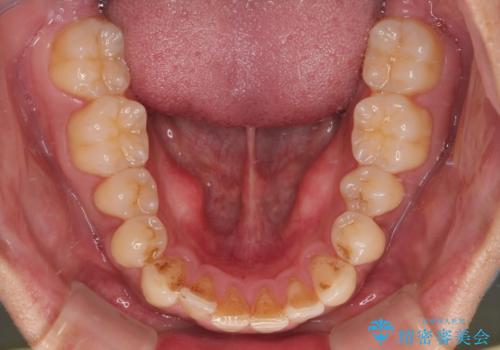

- 今回ご紹介するのは、

「過去に他院で矯正治療をしたものの、前歯の後戻りが気になってきた」

という理由でご来院された患者様です。

診察したところ、上下顎前歯部に軽度の叢生(ガタつき)が認められます。